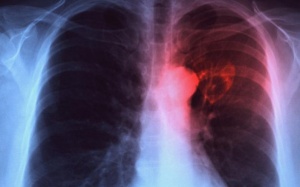

Lần đầu tiên trong lịch sử, bệnh lao đứng ngang hàng với HIV/AIDS và trở thành nguyên nhân gây tử vong hàng đầu trong nhóm các bệnh truyền nhiễm, theo báo cáo mới đây của Tổ chức Y tế...